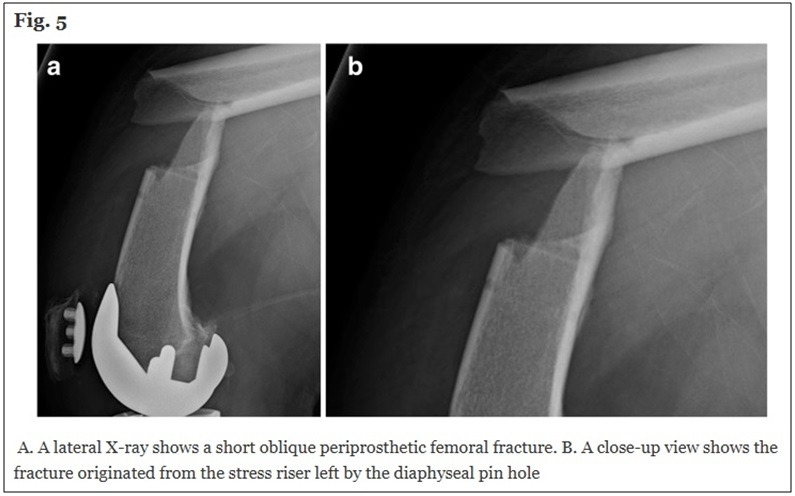

반면, 수술 시간이 길어짐에 따라 세균감염 위험이 높아지고, 로봇 수술에만 나타나는 합병증(e.g. 핀 홀 골절 -> 아래사진)도 생길 수 있기에 [20,21], 비싼 비용을 지불하고 거는 기대와는 달리 환자가 얻을 수 있는 실제적인 장점은 미미하다.

핀 홀 골절 : AG Yun et al. Arthroplasty 2021